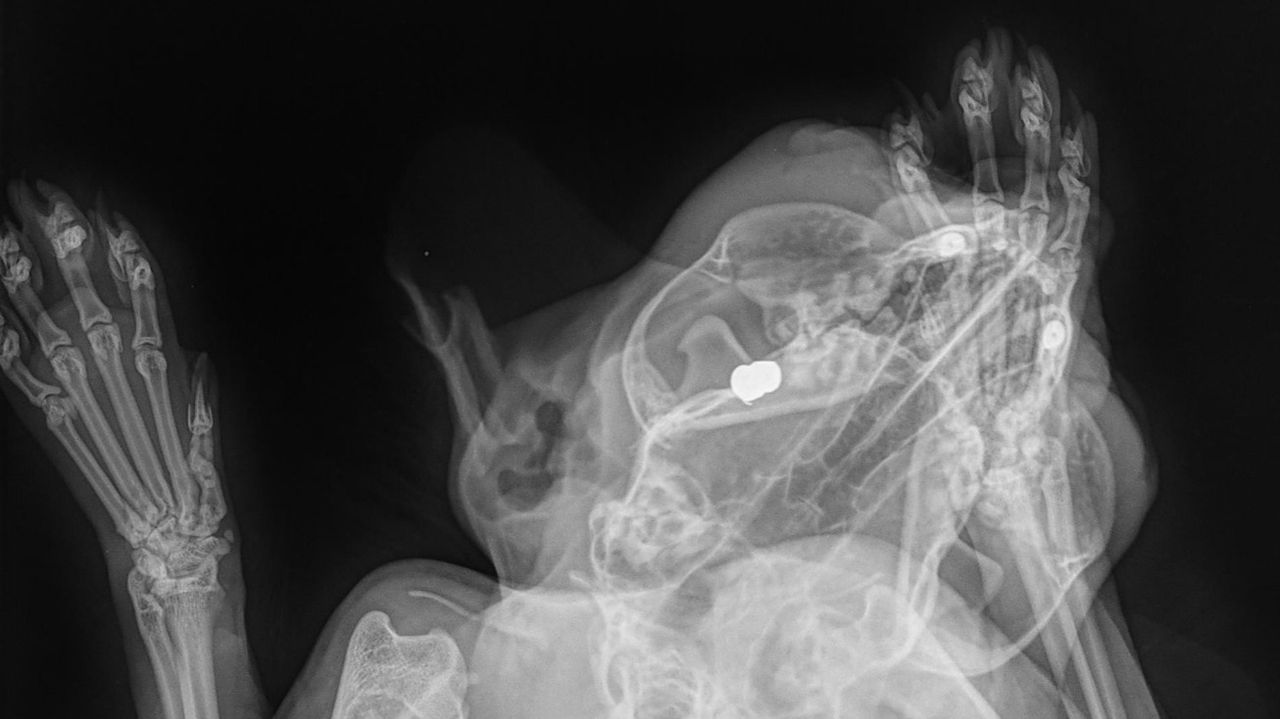

Kat Sonya werd beschoten met een luchtbuks: 'Kogeltje zat achter het oog'

Bij het dierenziekenhuis in Eindhoven is Sonya geopereerd. "Het oog was niet meer te redden door de schade", legt dierenarts Stijn Peters uit. "Het kogeltje zat echt achter het oog verstopt."

Let op: onderstaande foto's zijn schokkend.